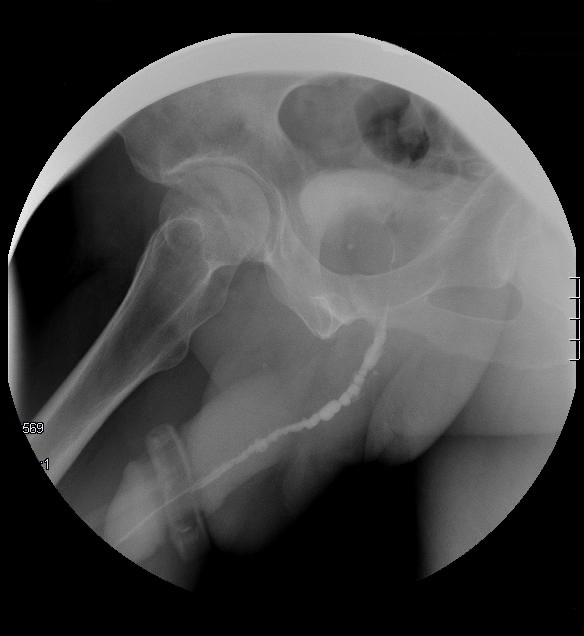

Cistouretrografía miccional seriada (CUMS)